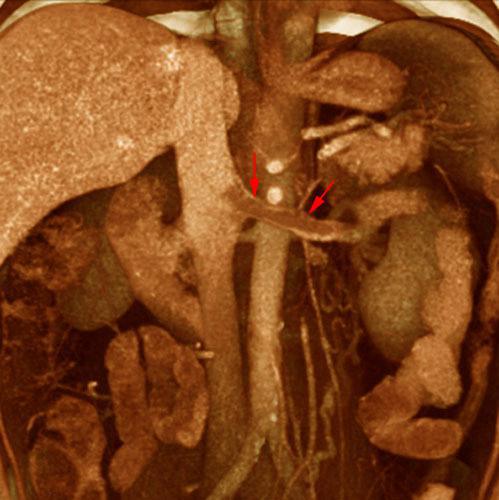

Síndrome del cascanueces